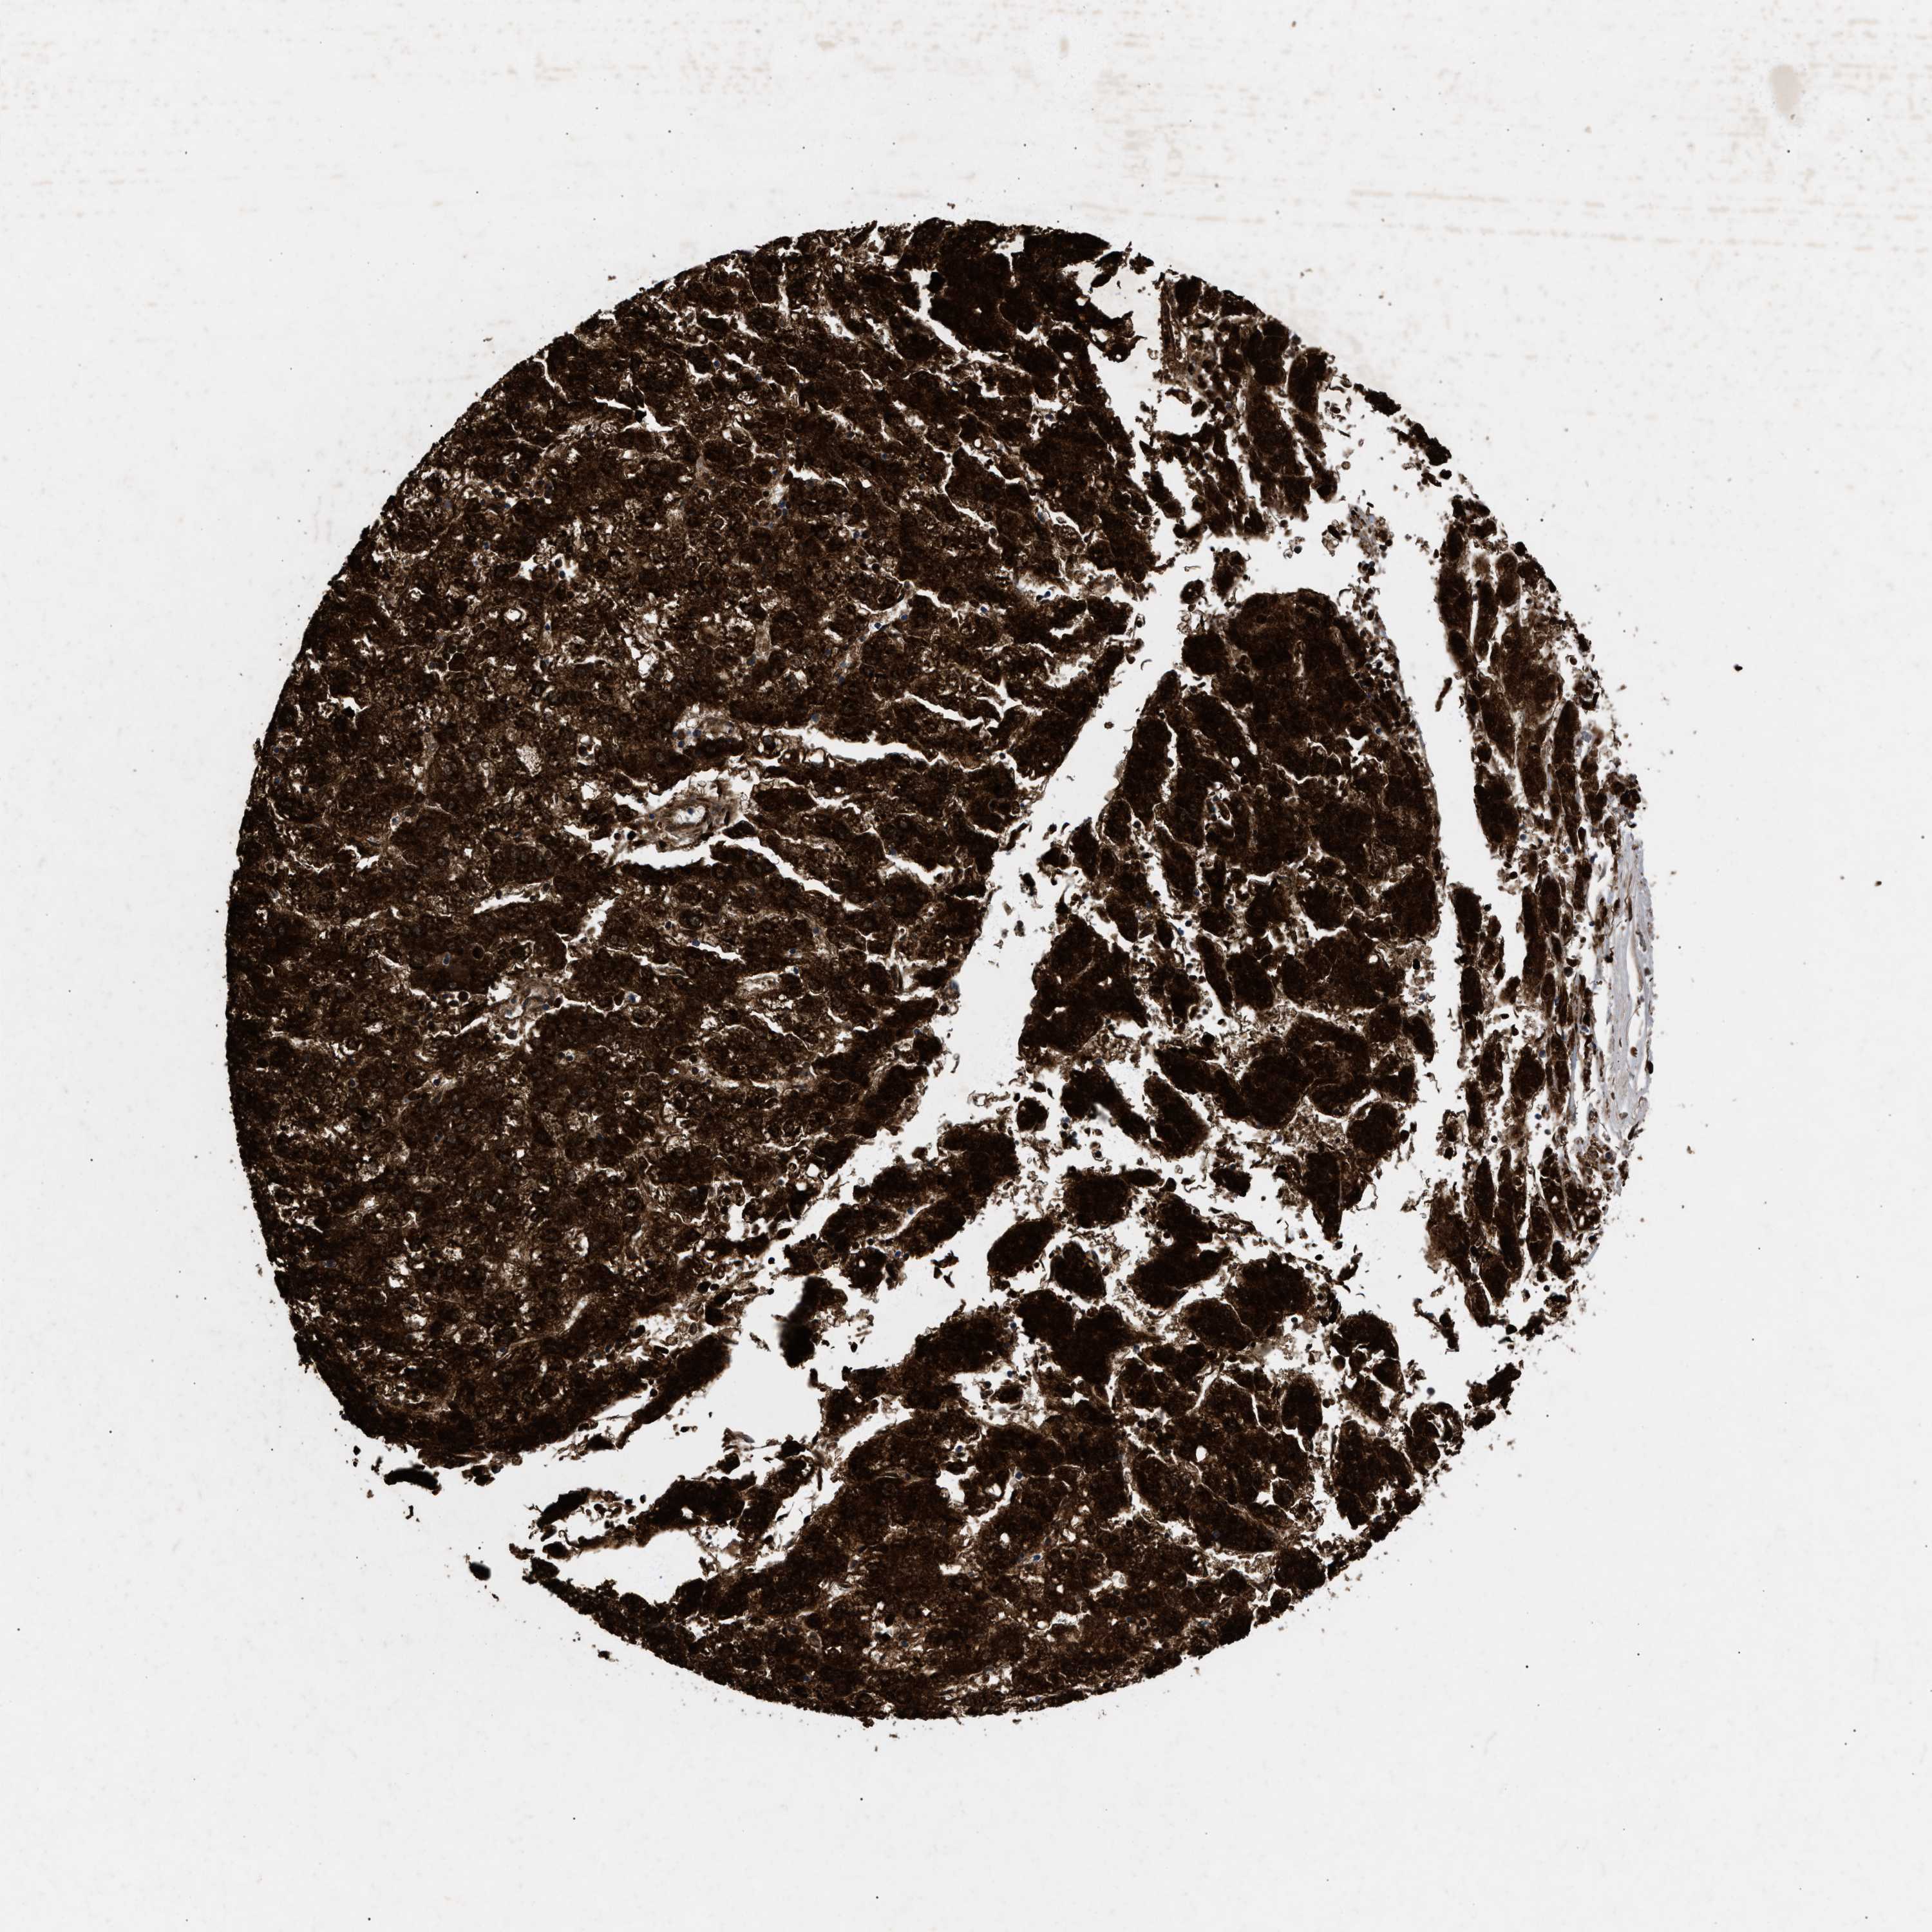

LIVER CANCER - Protein expressioni

A mouse-over function shows sample information and annotation data. Click on an image to view it in a full screen mode. Samples can be filtered based on level of antibody staining by selecting one or several of the following categories: high, medium, low and not detected. The assay and annotation is described here.

Antibody stainingi

Antibody staining in the annotated cell types in the current human tissue is reported as not detected, low, medium, or high, based on conventional immunohistochemistry profiling in selected tissues. This score is based on the combination of the staining intensity and fraction of stained cells.

Each image is clickable and will lead to virtual microscopy that enables deeper exploration of all samples and also displays staining intensity scores, fraction scores and subcellular localization as well as patient and tissue information for each sample.

Antibody HPA019369

Antibody HPA021323

Staining

High

Medium

Low

Not detected

Intensity

Strong

Moderate

Weak

Negative

Quantity

>75%

75%-25%

<25%

None

Location

Nuclear

Cytoplasmic/membranous

Cytoplasmic/membranous,nuclear

Cholangiocarcinoma

Carcinoma, Hepatocellular, NOS